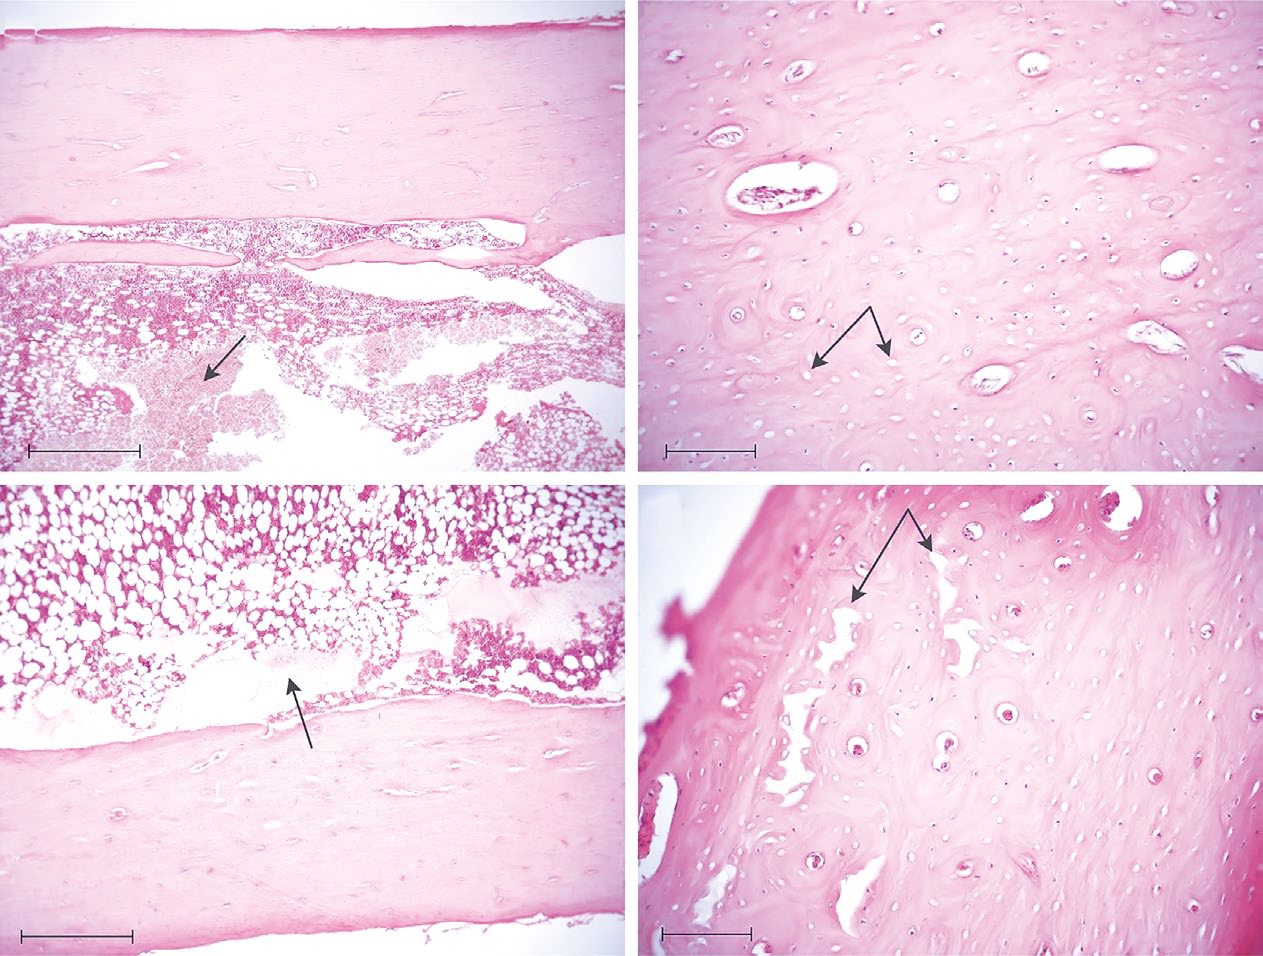

При окрашивании гистологических срезов бедренных костей кроликов по Эйнарсону была получена информация о содержании в ядрах остеоцитов молекул ДНК и, в меньшей степени, РНК. Поскольку остеоциты являются консервативной клеточной популяцией, для них не характерен высокий уровень синтетической активности, поэтому нуклеиновые кислоты визуализируются преимущественно в ядрах, а цитоплазма практически не окрашивается по методу Эйнарсона (рис. 8, a, c). В диафизе бедренной кости интактной конечности кроликов из группы 1 компактное вещество представлено преимущественно параллельно лежащими костными пластинками. Между костными пластинками визуализируются лакуны с остеоцитами, имеющими крупные округлые ядра, интенсивно окрашивающиеся по методу Эйнарсона (рис. 8, a). В компактном веществе интактной кости в группе 2 чаще встречаются остеоциты с вытянутыми, веретеновидными ядрами (рис. 8, c). В компактном веществе подвергавшихся нагреванию бедренных костей (рис. 8, b, d) на 3-и и 7-е сутки наблюдаются запустевающие лакуны остеоцитов либо остеоциты с вытянутыми, веретеновидными ядрами с визуально меньшей площадью окраски и оптической плотностью ядер в сравнении с соответствующим интактным диафизом (рис. 8, a, c).

Рис. 8. Участок компактного вещества диафиза бедренной кости: a — интактная кость кролика из группы 1, остеоциты с крупными, округлыми, интенсивно окрашенными ядрами (обозначены стрелками); c — интактная бедренная кость кролика из группы 2, остеоциты с веретеновидными, интенсивно окрашенными ядрами (обозначены стрелками); b — диафиз бедренной кости кролика из группы 1 через трое суток после нагревания при температуре в костномозговом канале 55–60 °C, запустевающие лакуны остеоцитов (обозначено стрелкой); d — диафиз бедренной кости кролика из группы 2 через семь суток после нагревания, остеоциты с менее интенсивно окрашенными веретеновидными ядрами (обозначены стрелками). Окрашивание остеоцитов по методу Эйнарсона, увеличение ×630

Fig. 8. A section through the compact substance of the femoral diaphysis: a — intact bone of rabbit from group 1, osteocytes with large, round, intensely stained nuclei (indicated by arrows); c — intact bone of rabbit from group 2, osteocytes with fusiform, intensely stained nuclei (indicated by arrows); b — femoral diaphysis of rabbit from group 1 three days after heating at a temperature in the medullary canal of 55–60 °C, deserted osteocyte lacunae (indicated by arrow); d — femoral diaphysis of rabbit from group 2 seven days after heating, osteocytes with less intensely stained fusiform nuclei (indicated by arrows). Osteocyte staining by the Einarson method, magnification ×630

Компьютерная морфометрия (табл. 3) демонстрирует одинаковое (p=0,28) уменьшение оптической плотности остеоцитов в прогретых диафизах у кроликов из обеих групп. При этом оптическая плотность остеоцитов подвергавшихся нагреву костей статистически значимо отличается от показателя в контрлатеральных диафизах (критерий Бруннера–Мюнзеля, p <0,05). К третьим суткам после гипертермического воздействия площадь остеоцитов резко снижается до 46,84[42, 29; 53, 29]% уровня в контрлатеральной кости; однако к седьмым суткам их размеры практически возвращаются к исходным значениям, достигая 108% показателя в контрлатеральном бедре. По аналогии с остеобластами можно предполагать быстрое обновление популяции остеоцитов крупными молодыми клетками с низкой синтетической активностью.